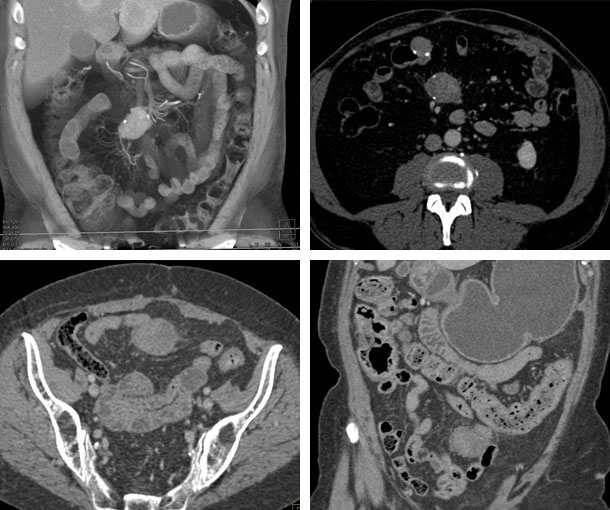

Mesenteric Desmoid Tumor CT Findings

- Soft tissue mass

- Ill defined margins

- Can be large, >15 cm

- Radiating fibrous strands that extend into surrounding mesenteric fat (“whorl appearance”)

- Isodense to muscle

- Can enhance heterogeneously or homogeneously